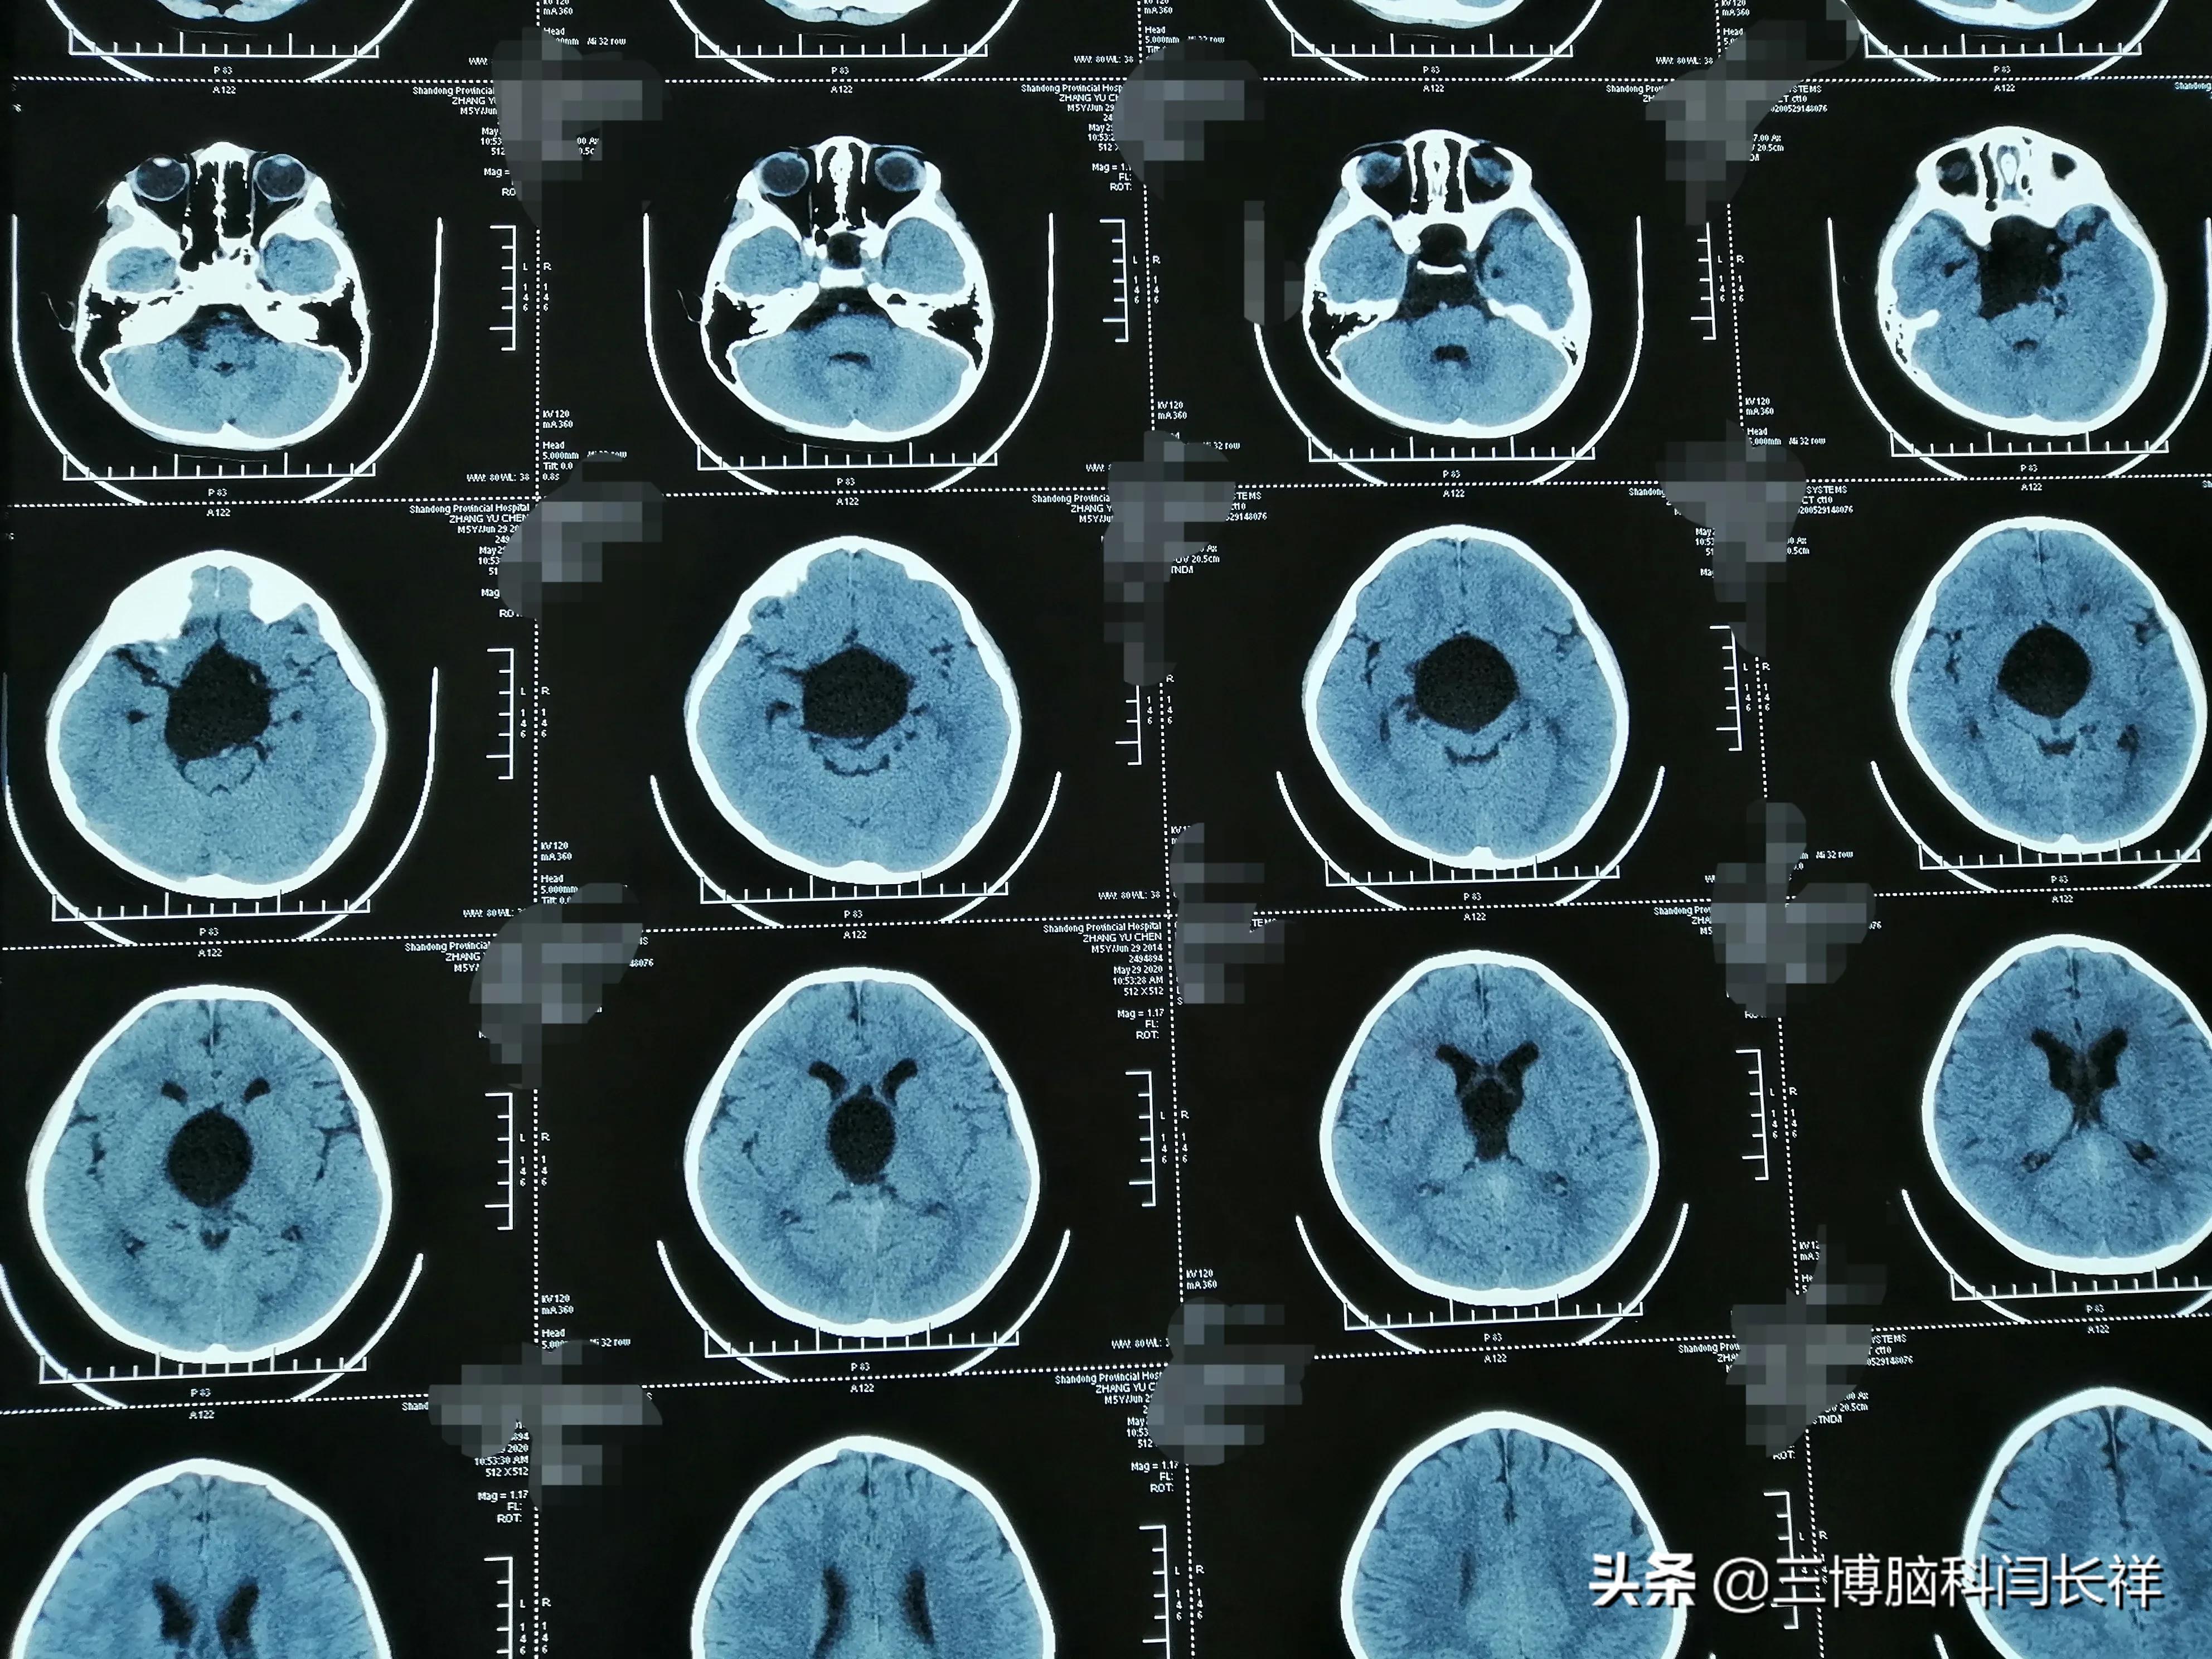

ct显示:四叠体区高密度影

蛛网膜下腔出血,鞍上池,四叠体池,双侧外侧裂池高密度.

蛛网膜下腔出血的ct表现 外侧裂,四叠体池出现高密度影